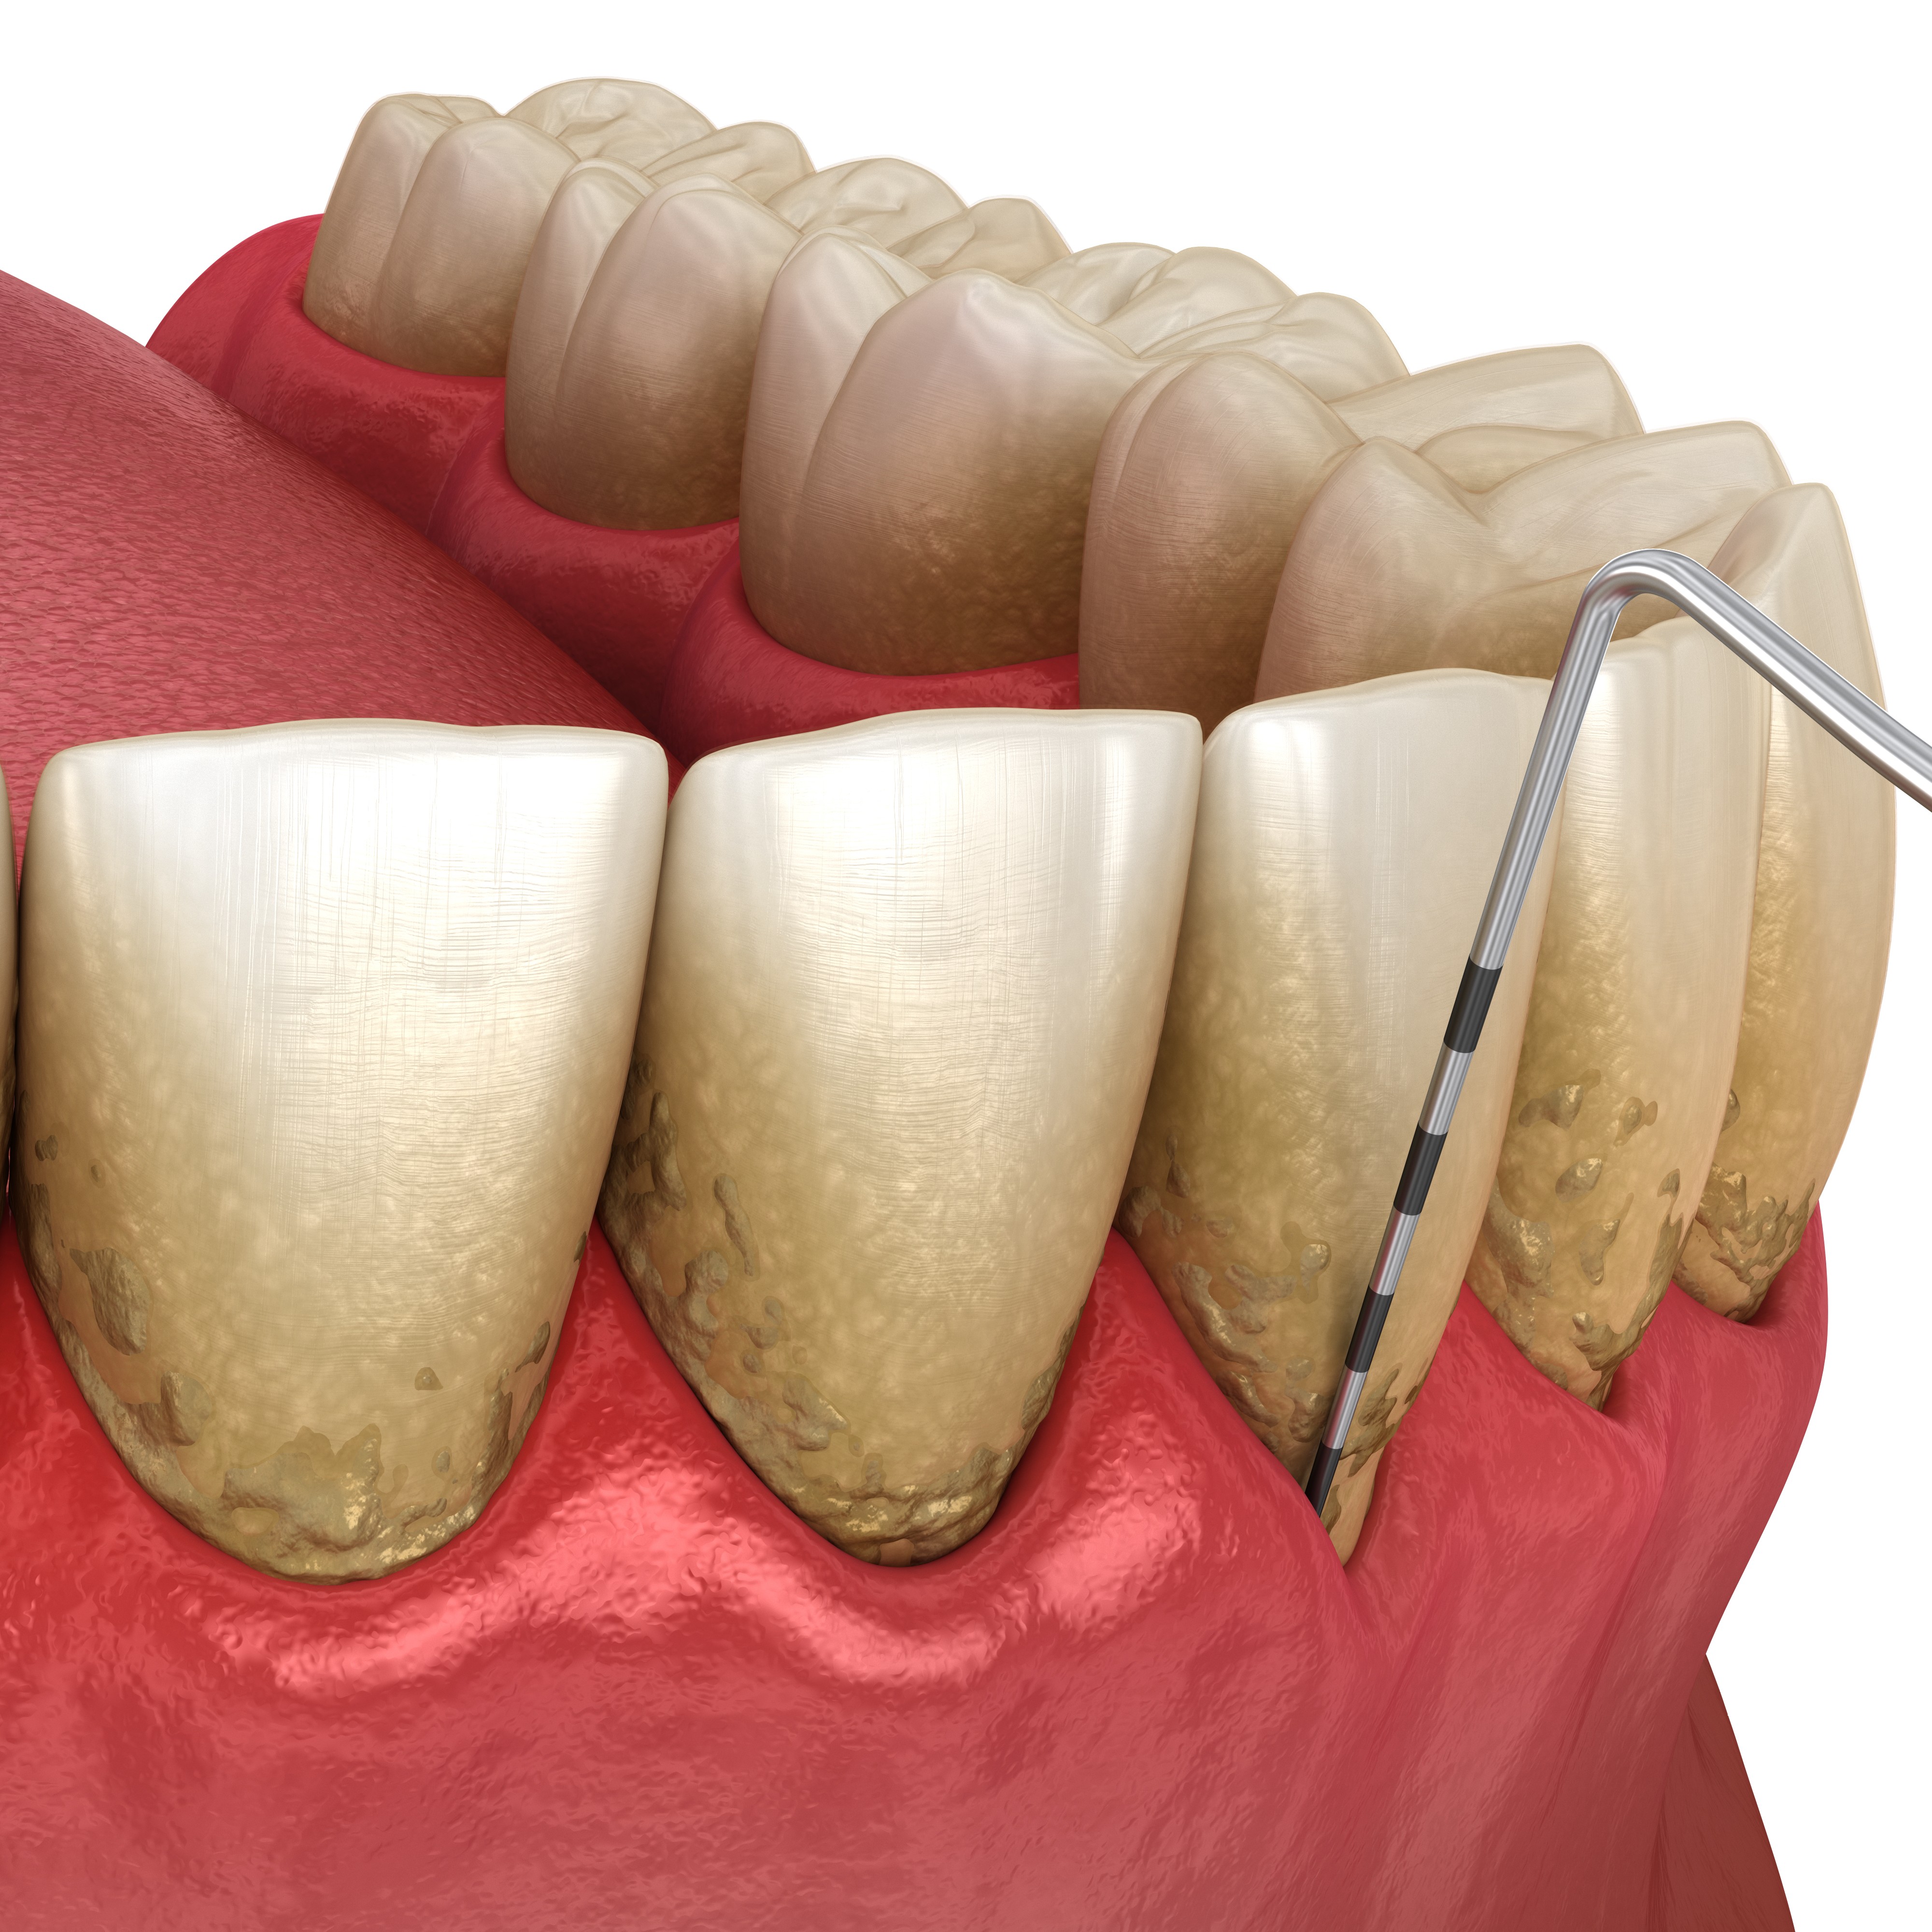

Fokus: Diagnostik, struktur og fælles behandlingsplanlægning

• Patientvurdering og parodontal diagnostik

• Systematisk journaloptag, risikovurdering og kliniske målinger

• Sådan stiller du en præcis og brugbar diagnose